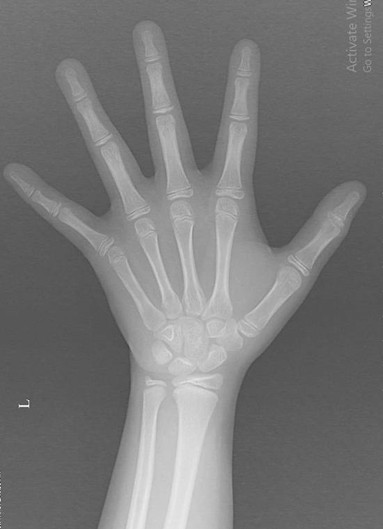

- Chụp Xquang xương cổ – bàn tay định tuổi xương có đang phát triển với tốc độ bình thường so với tuổi của trẻ hay không.

Hình ảnh minh họa Xquang xương bàn tay của bé gái 8 tuổi bị dậy thì sớm chụp tại khoa Chẩn đoán hình ảnh Bệnh viện Sản Nhi tỉnh Bắc Ninh

BS Ngọc Thị Huyền Diệu – Khoa Chẩn đoán hình ảnh